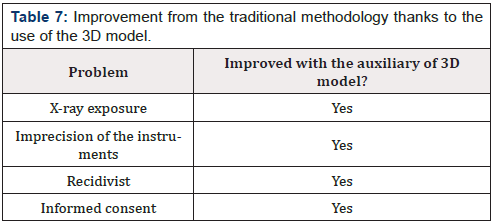

The use of 3D models during the pre-operative phase let surgeon proceed with more confidence during surgery due to increased knowledge of the anatomy of that specific case. One of the main advantages of this new method is the radiation time reduction [12]. With the new procedure the first RX scan is no more necessary, and the use of fluoroscopy should be reduced. In addition, the patient could learn the procedure to which he will be subjected interactively through a simulation on the prototype. All this has a positive impact on the hospital as it guarantees an improvement in the service for both patients and hospital staff. There is also a decrease in direct costs. The advantages obtained are summarized in (Table 7).

(Table 8) shows that problems of the traditional method are now solved with the introduction of three-dimensional anatomical model: